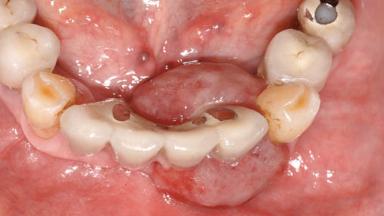

Peripheral Giant-cell Granuloma Associated with Peri-implant Tissues

Giant-cell granulomas (GCG) of the jaws are benign reactive lesions of unknown etiology, unrelated to giant-cell tumors (osteoclastomas), which are defined as benign but locally destructive and aggressive neoplasms (Jundt and coworkers 2005). Depending on their localization at the initial diagnosis, GCG are dived into central (CGCG) and peripheral (PGCG) types. CGCGs occur within the jawbones and appear as unilocular or multilocular radiolucent lesions. The incidence in the general population is very low. They are more commonly found in the mandible, mainly in children and young adults—patients are generally younger than 30 years—and have a greater incidence in females (Heithersay and coworkers 2002). The clinical behavior of CGCGs varies from slowly growing asymptomatic swellings to aggressive lesions that may result in pain, cortical perforation of the affected jaw site, and root resorption (de Lange and coworkers 2007).